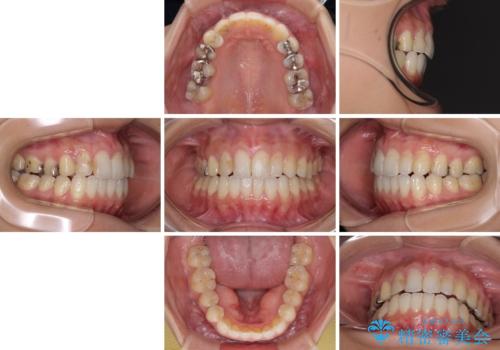

- 中学生の時に矯正治療をしたものの、後戻りを気にして来院された患者様です。

骨格的に下顎が右側に変位しているため、左右の咬み合わせを理想的なものに改善することはできませんが、インビザラインにて歯列を整えることとしました。

骨格的なズレによる左右差は改善できませんでしたが、上下の正中を極力合わせるようにすることができました。